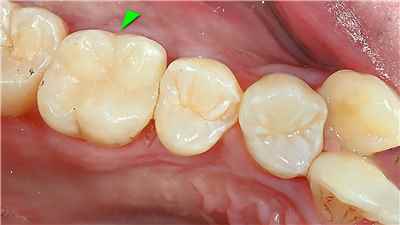

치아 변색 외부 요인